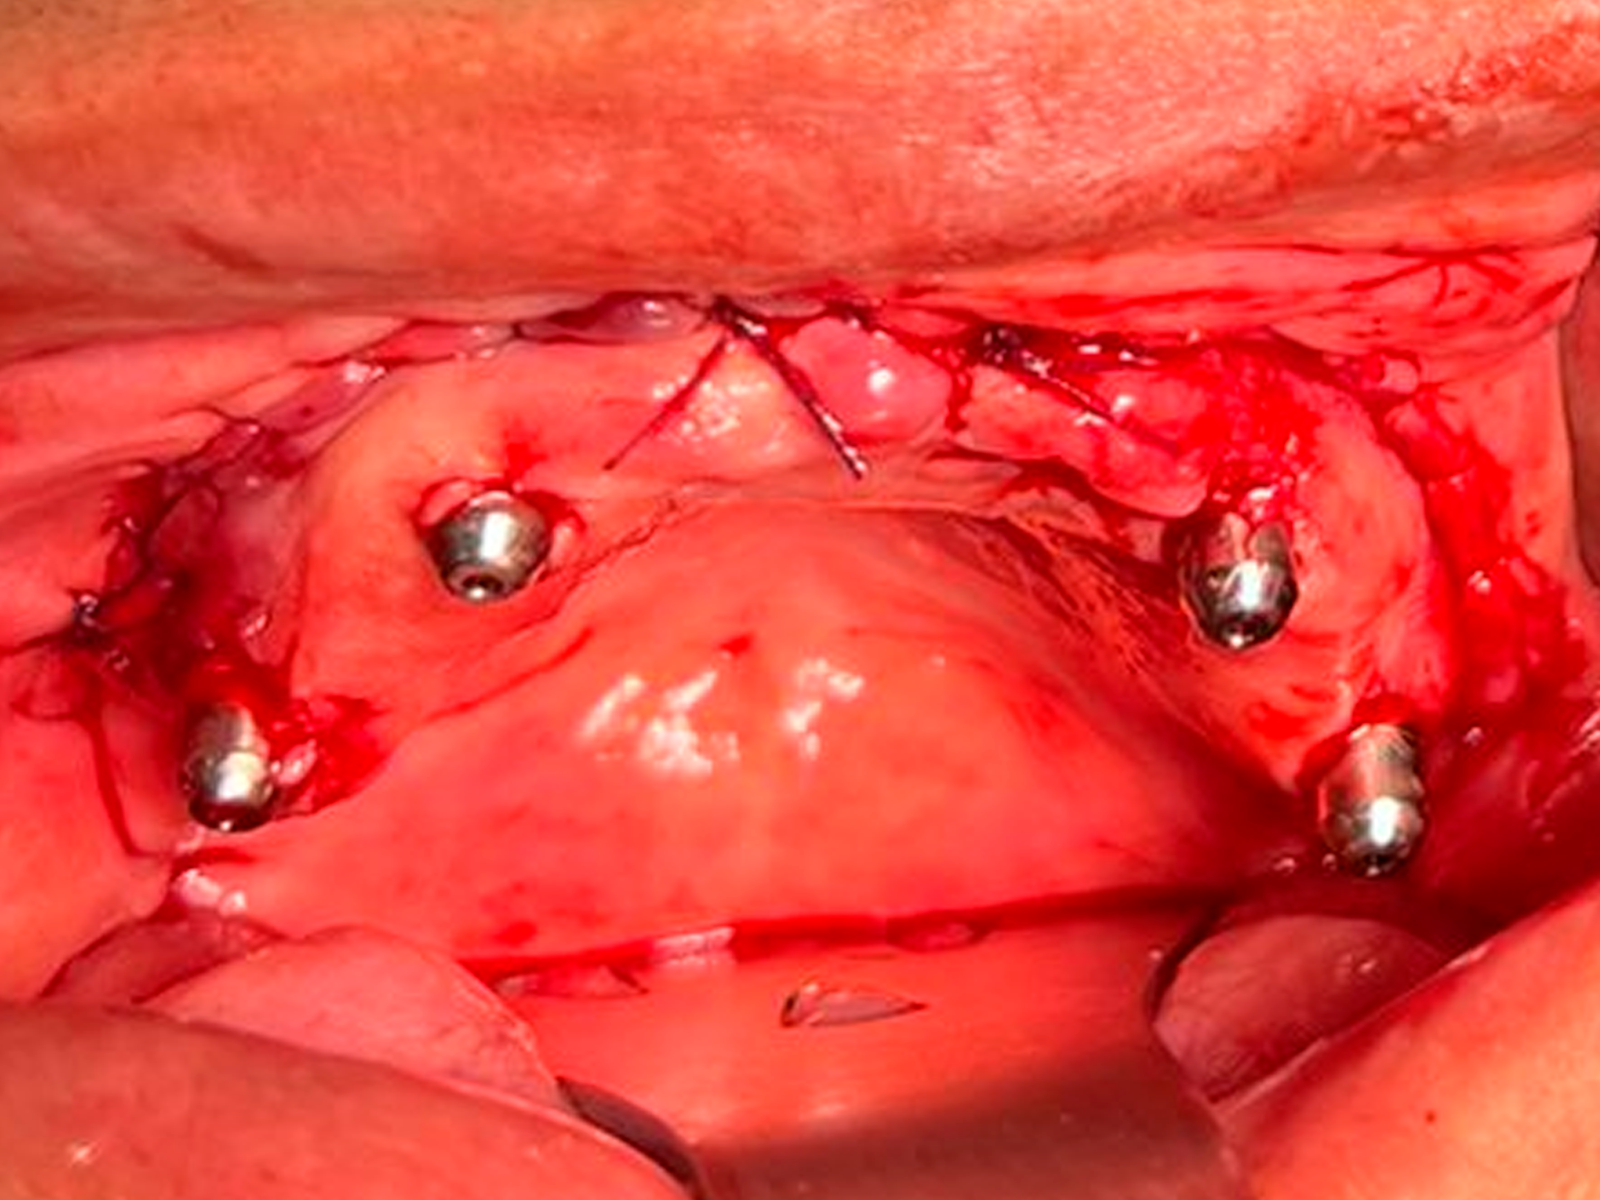

CUSTOMLIFE NA PRÁTICA

Confira case cirúrgico

Reconstrução de Maxila Total